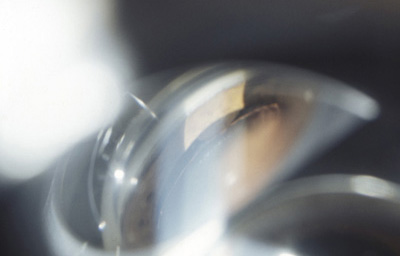

Melanoma sólido nodular del Iris

Melanoma sólido nodular del Iris con lente de Gonioscopía

Archivo Fotográfico Dr. Francisco Barraquer.